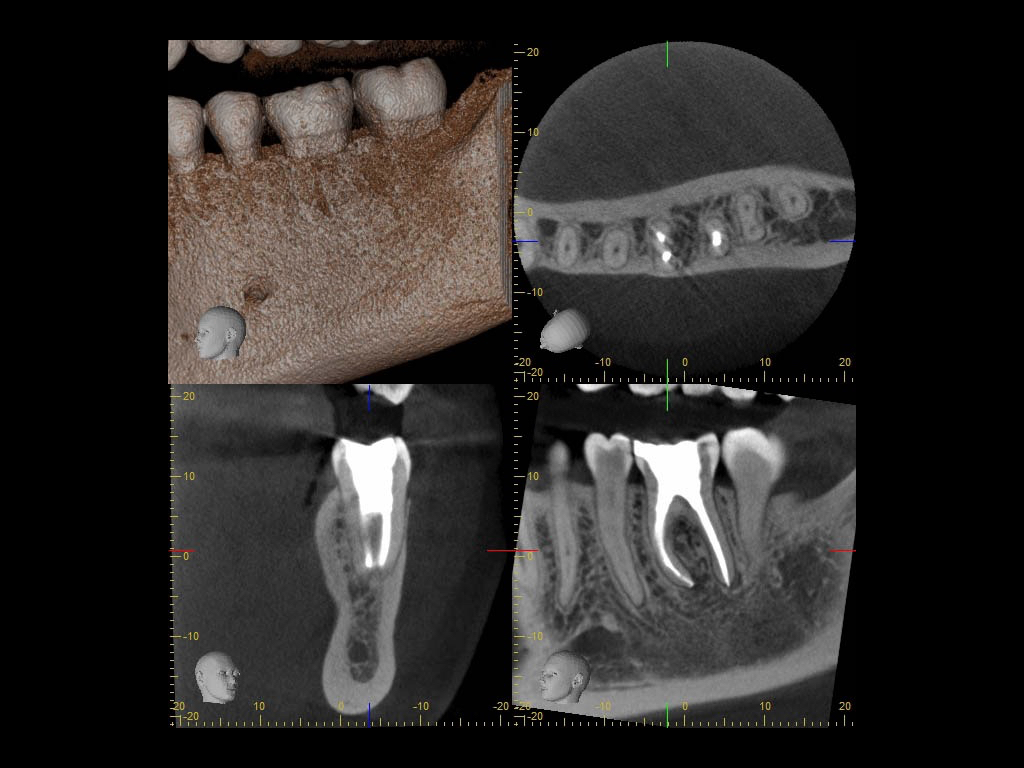

Calciumhydroxid – Überpressung (1)